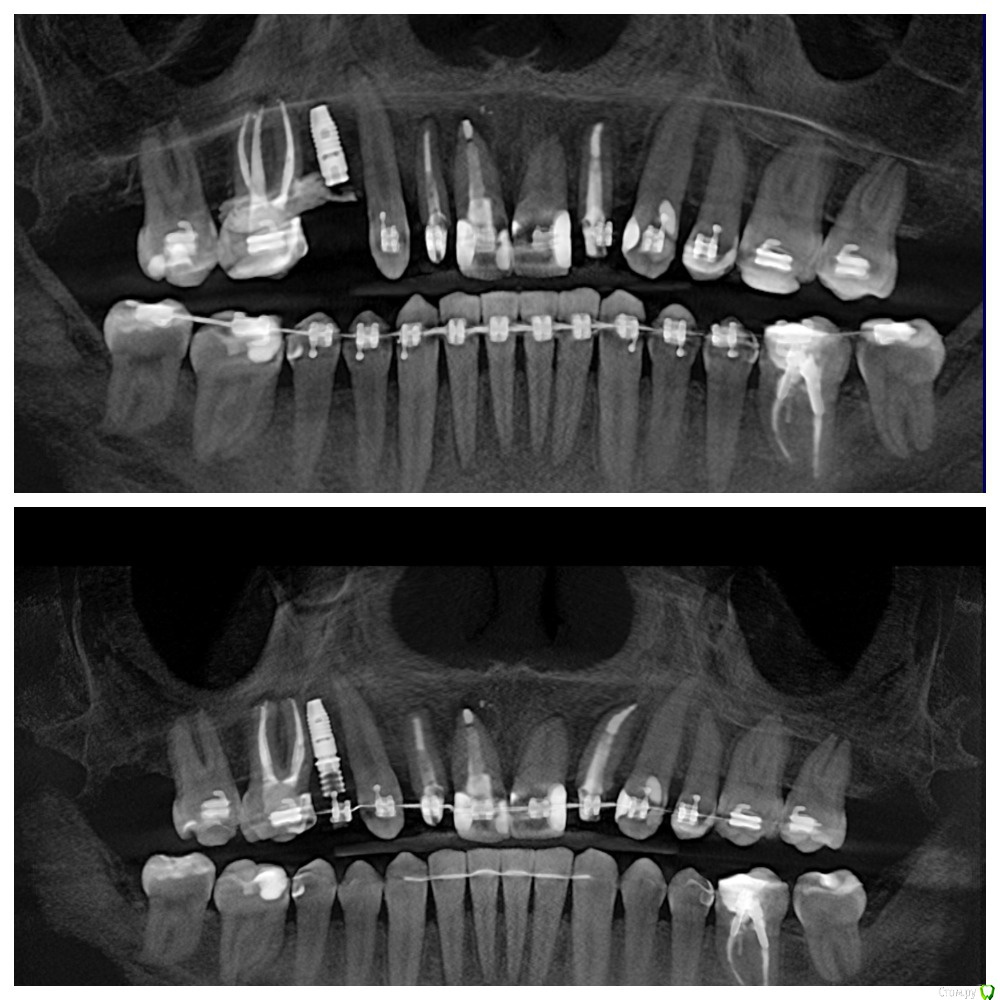

Al..ks Опубликовано 28 мая, 2020 Поделиться Опубликовано 28 мая, 2020 (изменено) Добрый день. Нужен совет. В августе 2019 года, во время установки формирователя десны чистили десневой карман у 17 (грануляции и тд) и подсыпали туда материал какой то, чтоб кость нарастить. А через пол года был план - осмотр и возможно еще подсыпать.К сожалению врач, которая это делала ушла из клиники и на консультацию через полгода пошел уже к другому.Он сделал КТ (зондом не смотрел карман) и сказал , что ничего не надо больше подсыпать, только наблюдать. Меня немного морочит - зуб немного шатается, и полость полностью не заросла костью.Вот фото КТ (сверху было, снизу стало) Изменено 28 мая, 2020 пользователем Al..ks Ссылка на комментарий

Irouil Опубликовано 29 мая, 2020 Поделиться Опубликовано 29 мая, 2020 У 1.7 зуба ничего "подсыпать" не нужно Ссылка на комментарий

krokomot Опубликовано 29 мая, 2020 Поделиться Опубликовано 29 мая, 2020 карман этот в следствии перегрузки зуба, нужно проверить суперконтакты на 7-м Ссылка на комментарий

Al..ks Опубликовано 29 мая, 2020 Автор Поделиться Опубликовано 29 мая, 2020 карман этот в следствии перегрузки зуба, нужно проверить суперконтакты на 7-мНе совсем - он образовался давно, а обнаружили когда 18 удалили - там отсутствовала стенка костная и было куча грануляций - еще до брекетов. У 1.7 зуба ничего "подсыпать" не нужно Спасибо Ссылка на комментарий

Al..ks Опубликовано 5 июня, 2020 Автор Поделиться Опубликовано 5 июня, 2020 Если вы и сами во всем разбираетесь, то зачем спрашиваете совета?, если бы у вас зуб был без перегрузки, то он бы не шатался.По этому снимку вся же предистория не видна (до брекетов - где не понятно как были контакты было: - 16 резорцинформалиновый сильно наклонен, 17, 18. Между ними иногда кровило при чистке ирригатором. 18 заболел перед самой установкой - удалили и в процессе выяснилось - нет костной стенки между ними и когда все зашили и зажило,то остался карман глубиной где-то 11мм. Ну а дальше .... Сейчас (когда его "отключили" от дуги) он шатается уже не так сильно, но по ощущениям чуть сильнее чем "подключенные" к дуге брекетов. Ссылка на комментарий